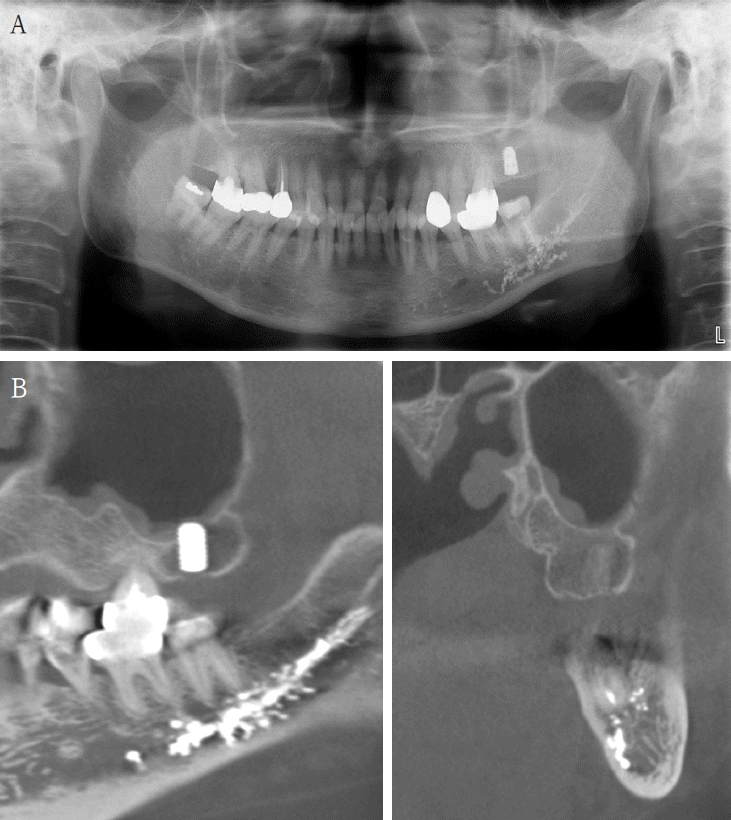

A 61-year-old female presented with intermittent right mandibular swelling and pain after root canal therapy was done using EndoSeal MTA 5 months ago. A panoramic radiograph, CBCT and bone scan confirmed material extrusion and mild localized bone changes (Fig. 4). Initial neurologic evaluation demonstrated nearly normal sensory function, with Visual Analog Scale (VAS) 4 discomfort. Surgical curettage was performed under local anesthesia. A post-operative panoramic radiograph confirmed the substantial removal of the foreign body (Fig. 5). Postoperatively, the patient reported significant improvement at both the one- and two-month follow-ups. Due to full symptom resolution, no follow-up neurosensory testing was performed.- Case 4

Figure 4.

A. Pre-op panoramic radiograph of Case 3 patient. B. Pre-op CBCT of Case 3 patient. C. Pre-op bone scan of Case 3 patient